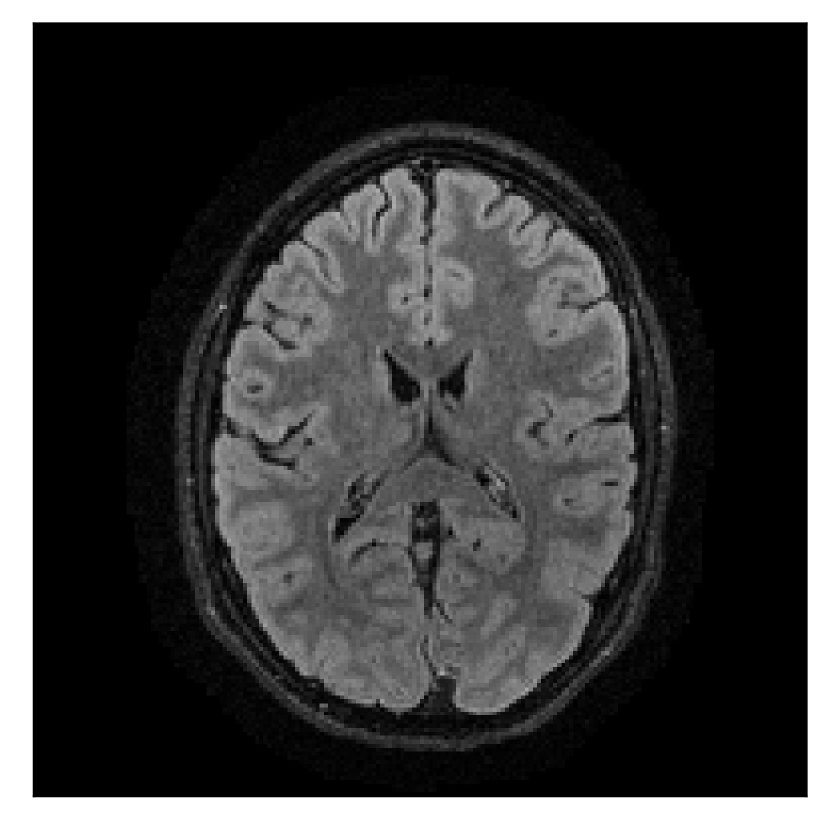

4.2 Experiment 2: choice of the reference contrast

With the experiment described in Section 3.2, we demonstrate the flexibility of the correction scheme with respect to the choice of the reference contrast. The results are shown in Figure 10. Contrary to the experiments detailed in the previous section, we are now considering a T2-weighted reference contrast to guide the correction of a T1-weighted corrupted contrast. The quality of the correction indicates that the proposed technique is rather flexible in terms of reference contrast.

| Section 3.2, Figure 10 | Sagittal | 25.84 | 28.07 | 0.7032 | 0.8093 |

| Coronal | 26.35 | 30.40 | 0.7851 | 0.9021 | |

| Axial | 28.11 | 30.54 | 0.8248 | 0.9012 | |

| Section 3.2, Figure 10 | T1 | Completely corrected | Some blurring | No additional artifacts | Good grey white matter differentiation, |

| some loss of grey matter low signal | |||||